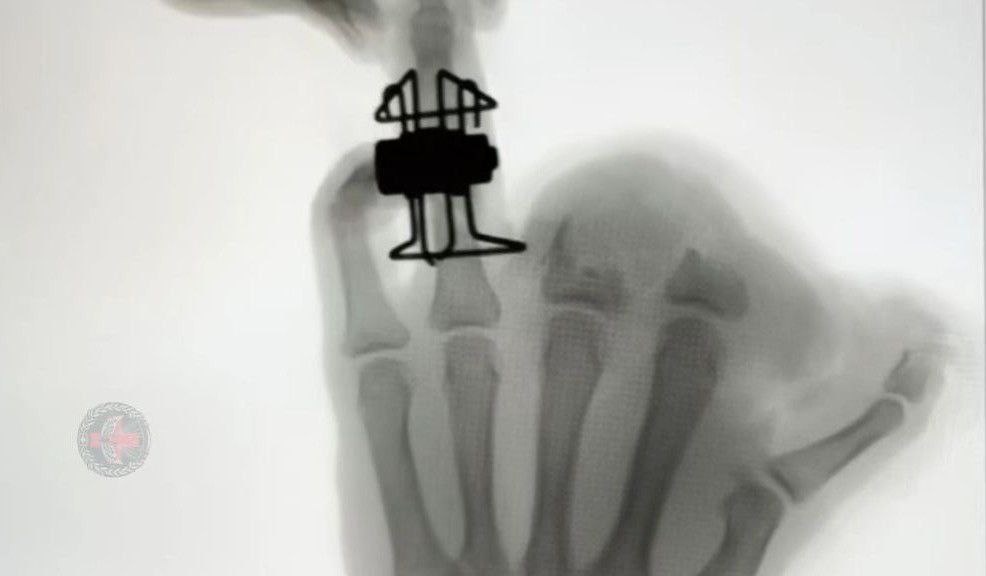

⚠️ Тульские медики создали новый аппарат для лечения переломов Военные врачи 39-го медотряда ВДВ разработали: • Улучшенную версию аппарата для лечения сложных переломов пальцев • С точной регулировкой силы воздействия • Уже применяется в зоне СВО Актуальные новости — в Тула Шум.

• Улучшенную версию аппарата для лечения сложных переломов пальцев

• С точной регулировкой силы воздействия